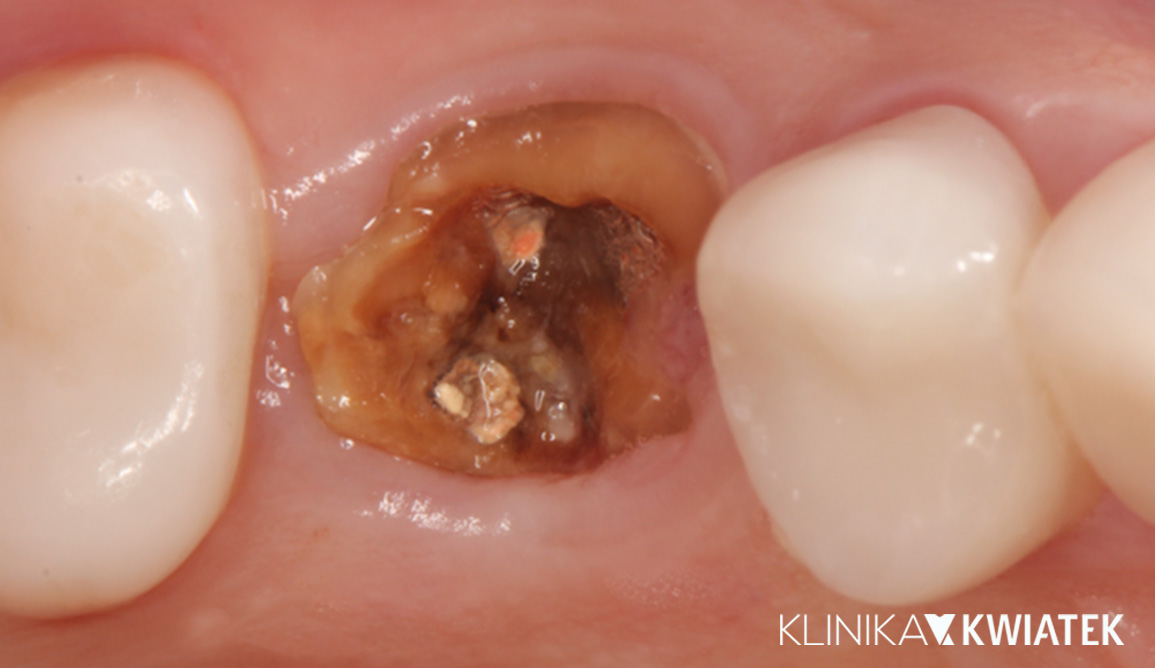

Kiedy ząb nie ma już szans… wykorzystujemy potencjał implantologii - odbudowa 26

Kategoria: Implanty, Korony i mosty

Pacjentka zgłosiła się z nawracającymi dolegliwościami bólowymi oraz zmianą okołowierzchołkową przy zębie 26. Pomimo podjętej próby powtórnego leczenia kanałowego pod mikroskopem, nie udało się wyleczyć zęba, dlatego zadecydowano o jego ekstrakcji i wykonaniu odbudowy implanto-protetycznej. Finalnie przeprowadzono implantację MIS z augmentacją oraz osadzono pełnokonturową koronę cyrkonową, przywracając pełną funkcję i estetykę.